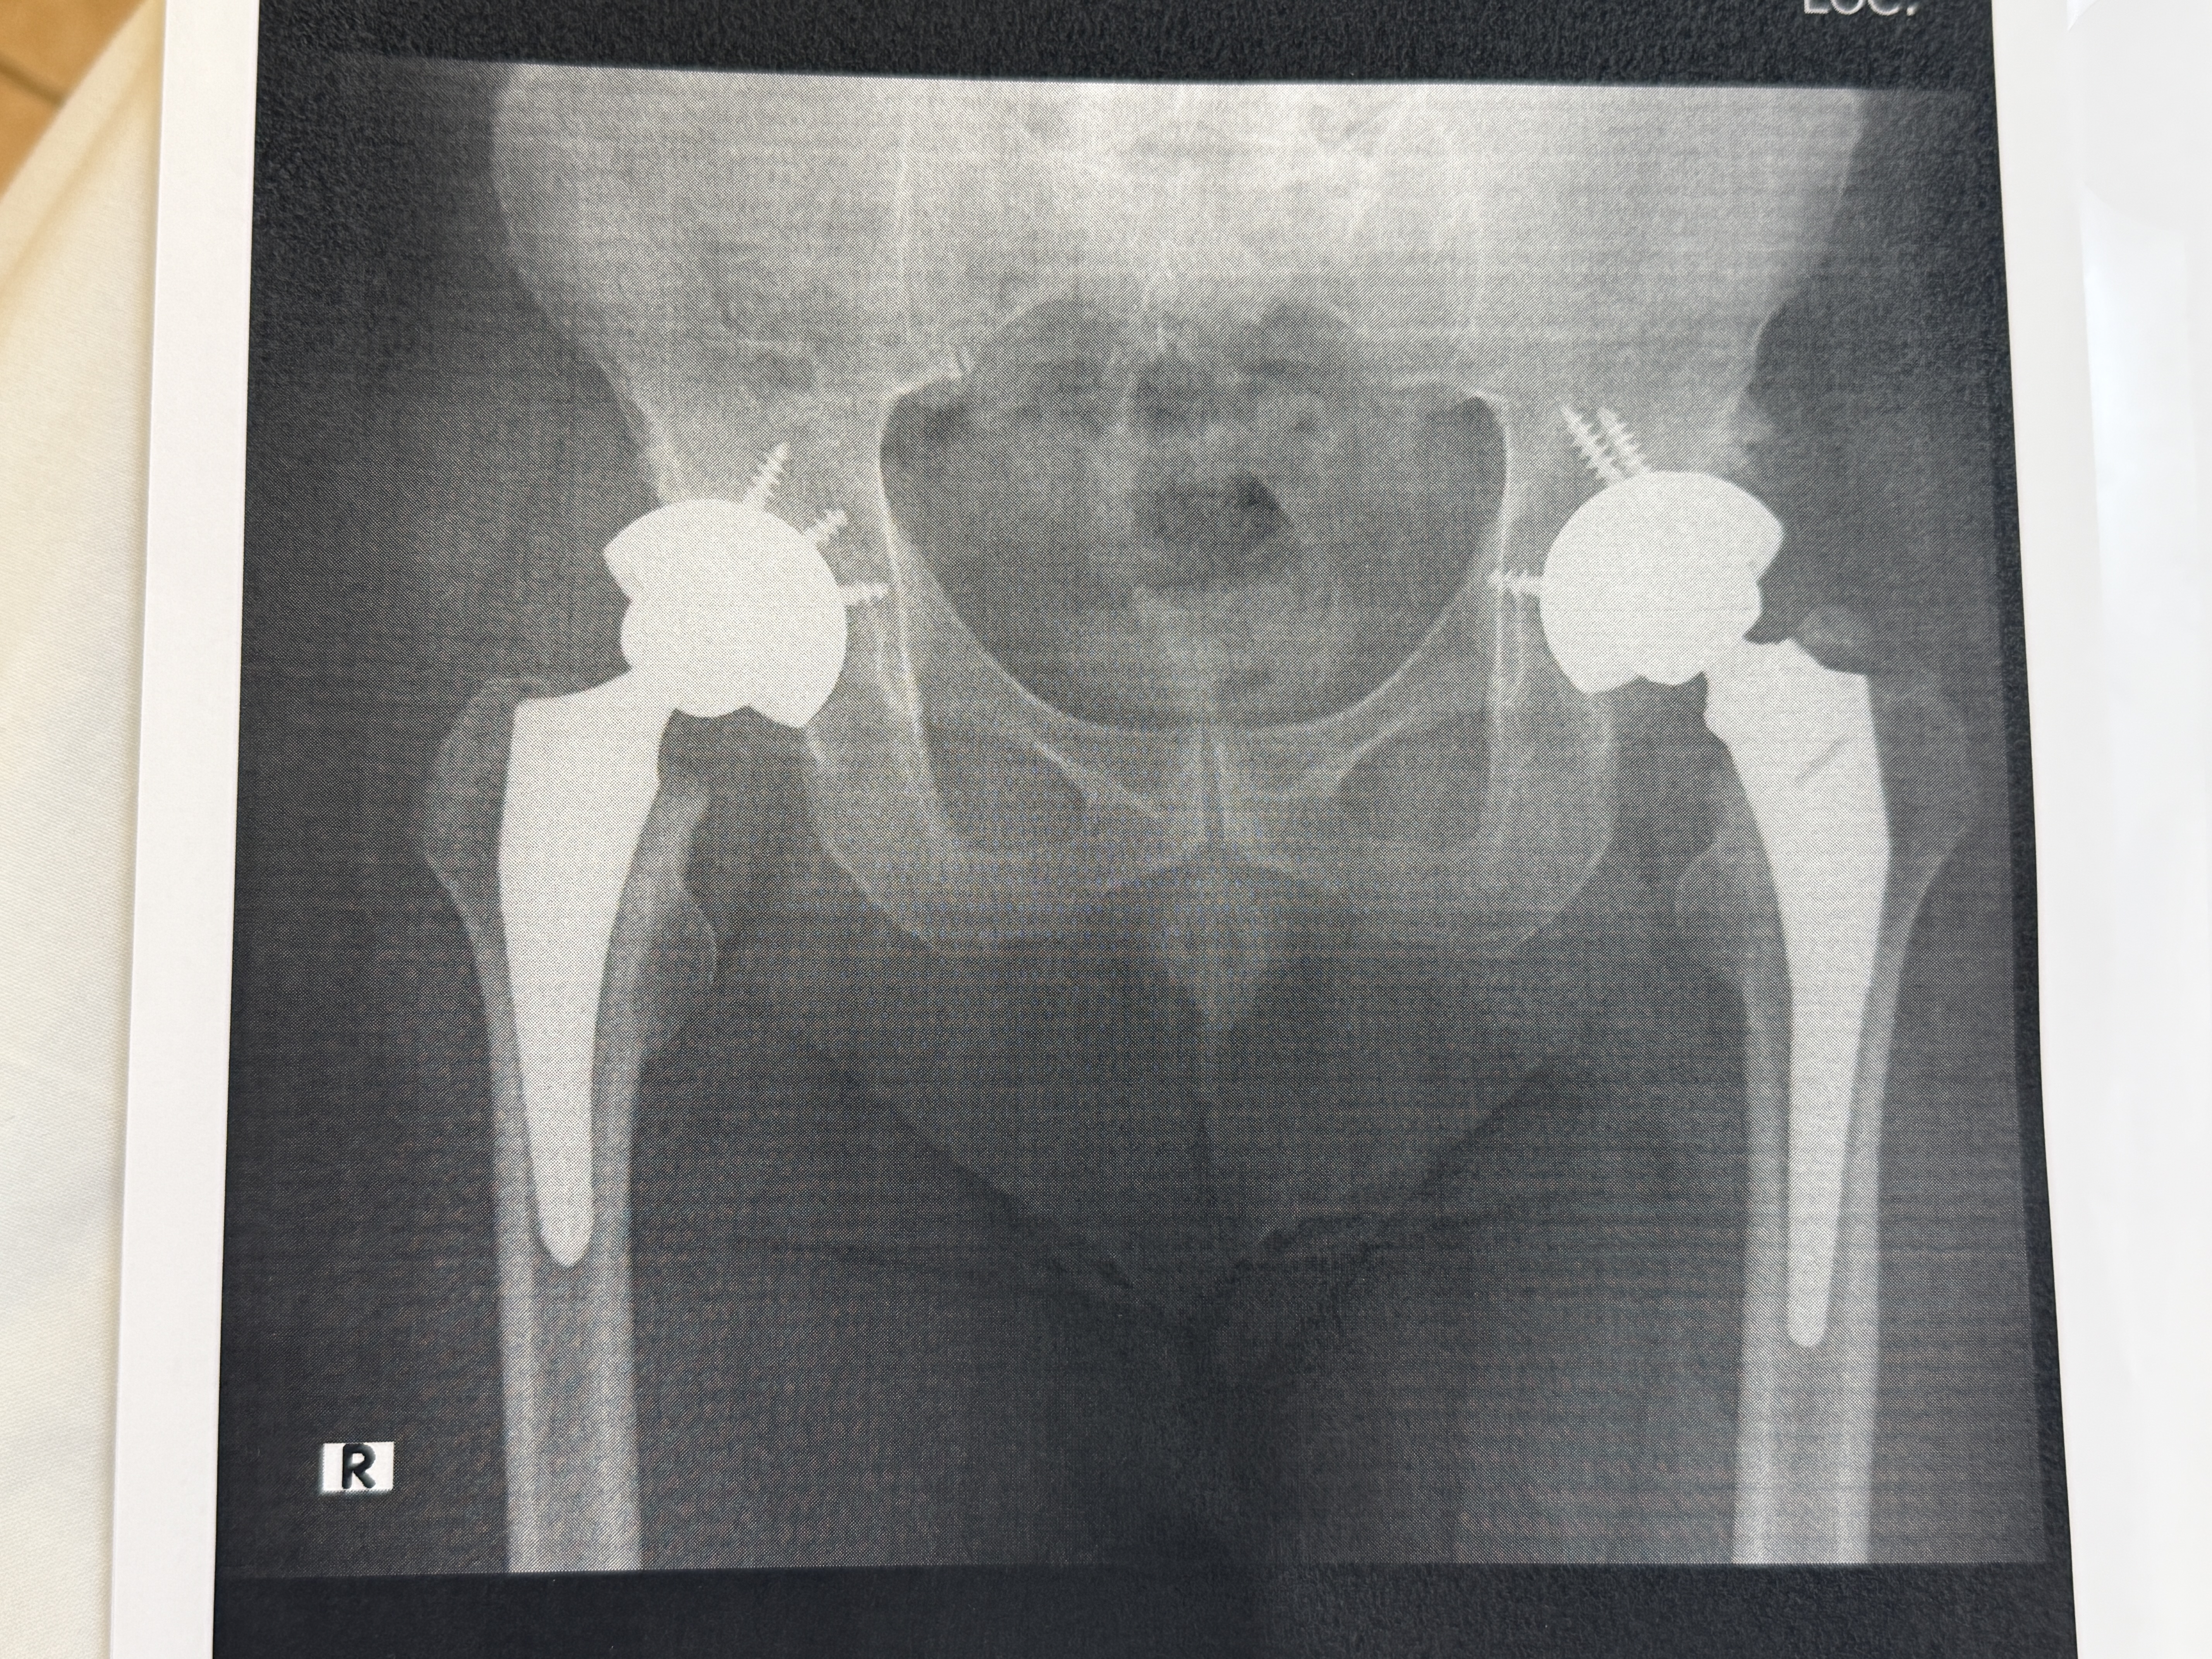

49911.jpg (7228KB) 手術終わってリカバリー室です。

取り敢えず、生還おめでとう!

[10] 投稿者:顧問ちゃま 投稿日:2026/02/03 (火) 16:40 No.49913

黒点が成長しています!

そもそもカリスマ性が欠けているよなぁ。

今はレントゲンもデジタルなんですね、実費ですが希望すればレントゲン画像をCDRに焼いてもらえるそうです。

人口関節 レントゲンで見るとすごいですね。